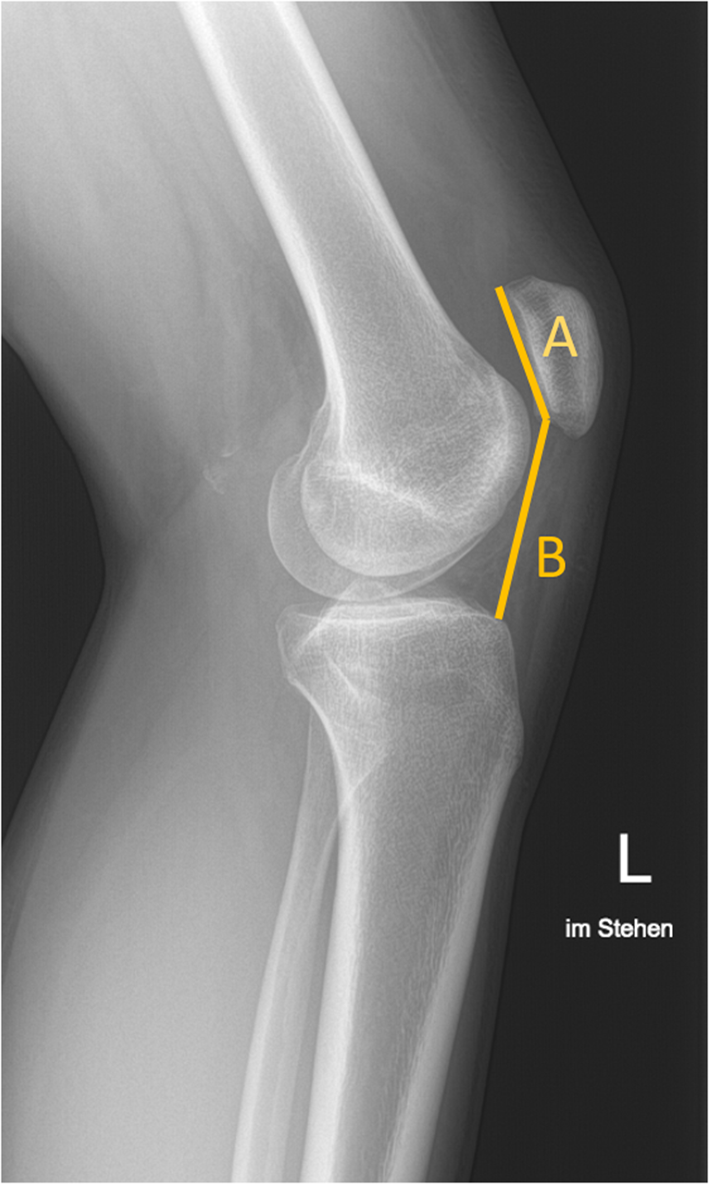

The traditional CD assessment of patellar height was performed on lateral X-rays (Fig. 1) [10, 14]. The CD is obtained by measuring two different parameters; (1) the length of the articular surface of the patella and (2) the distance between the inferior aspect of articular surface of the patella and the anterior angle of the tibial plateau.

Fig. 1

Conventional X-Ray lateral view. Cato–Deschamps (CD) index measurement. A patellar length, B distance from the patella to the tibia. CD: B/A